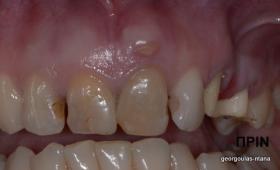

Στην ασθενή αυτή είχαν πραγματοποιηθεί 2 ενδοδοντικές θεραπείες (απονευρώσεις) που ακολουθήθηκαν από 2 ακρορριζεκτομές χωρίς επιτυχία. Η ασθενής ήταν δυσαρεστημένη με την όψη κ το χρώμα των δύο δοντιών και φυσικά με το πρόβλημα υγείας που δημιουργήθηκε. Πραγματοποιήθηκε εξαγωγή των δύο δοντιών, οστική αύξηση και τοποθέτηση 2 εμφυτευμάτων στις θέσεις των δύο κεντρικών τομέων. Τα δύο εμφυτεύματα αποκαταστάθηκαν με 2 υβριδικά κολοβώματα από διπυριτικό λίθιο και ολοκεραμικές στεφάνες ενώ στους 2 πλάγιους τομείς τοποθετήθηκαν επίσης ολοκεραμικές στεφάνες.